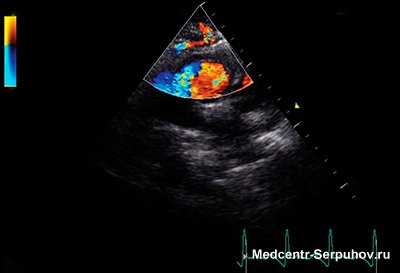

Основной диагностический метод эхокардиография - позволяет подтвердить диагноз и определить превалирующий порок. Характерны патогномоничные для митрального стеноза замедление раннего диастолического прикрытия передней створки митрального клапана, движение которой приближается к П-образному, и смещение кпереди его задней створки параллельно движению передней. Створки утолщаются, и амплитуда диастолического открытия клапана уменьшается. Полость левого желудочка может увеличиваться у размерах в зависимости от выраженности регургитации и миокардиальной недостаточности. Допплерэхокардиография позволяет оценить диастолический градиент давления на митральном клапане и величину обратного тока. В неясных случаях выраженность стеноза и регургитации уточняют при катетеризации сердца и ангиокардиографии.

ЭхоКГ-признаки поражения митрального клапана:

- наличие митральной регургитации, степень которой зависит от тяжести поражения;

Эхо-КГ признаки поражения аортального клапана:

- аортальная регургитация (направление струи к передней митральной створке);

- высокочастотное трепетание (флатер) передней митральной створки вследствие аортальной регургитации.